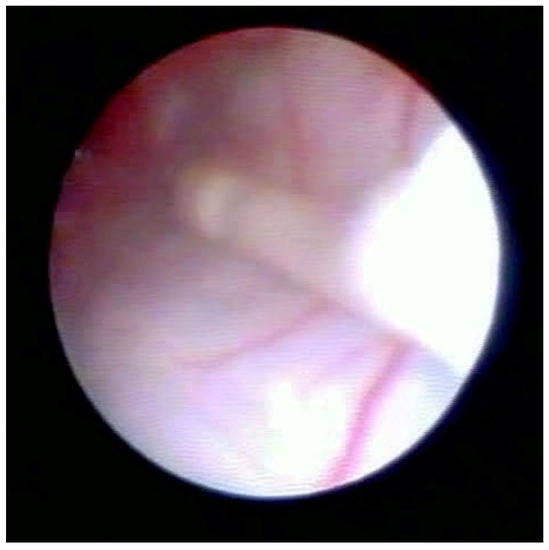

Figure 2 shows the lifting of the meningeal dura for dural mobility abnormalities with an underlying lifting of the spinal root, which determines a pseudo-lifting of the dura, potentially resulting in a false diagnostic radiology interpretation of a median ligament. Moreover, the presence of a Fogarty catheter inside the bed of the dura in the midline causes lifting of the dura mater in relation to the root below, which can mimic a false longitudinal ligament in radiodiagnostic imaging (Figure 3). Morphological analysis of the pathological spaces also showed that, in these cases, no segmentation occurred. The left side of Figure 4 shows a fibrotic septum grafted on the dura. However, underlying dural bases exhibit no segmentation.

In accordance with Hogan [9], we believe that the membrane could be attributed to raising of the dural cloth due to pressure secondary to the use of rigid instruments on the dura (Figure 3). Moreover, in the presence of tractions secondary to pathological events (such as post-surgical or post-inflammatory fibrosis) on the dura mater, the membrane could be raised by generating, with its “sail” shape, a segmentation-like feature [16] (Figure 4). Hogan claimed that in addition to the absence of any “fibrous barrier across the intervertebral neural canals” a narrow fibrous band could sometimes be seen adjacetn to the superior edge of pedicle epidural space … and epidural space is widely open on its lateral aspect” [8]. Asato published a paper indicating that no obstacle existed to the spread of epidural solution due to a median epidural septum, and the epidurography, performed in seven patients with unilateral epidural block, showed that the cause of the unilateral block was the placement of the catheter into the anterior or transforaminal epidural space [18]. Transversal segmentation, which divides the space into two sections, can be present in subjects with diseases secondary to chronic polyfactorial stenosis or where previous spinal surgery justifies abnormalities in fluid distribution, based on the CT findings by Savolaine [7].

Figure 3. Fogarty catheter close to dura.